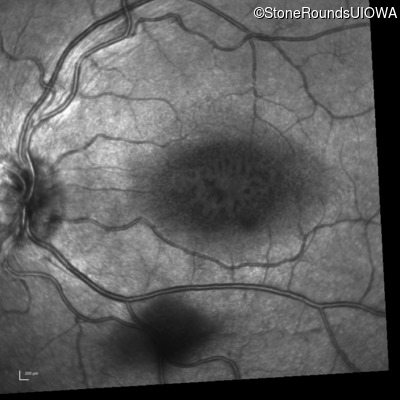

Infrared Fundus Photograph - Left - 20/70 +1 sc

Exemplar